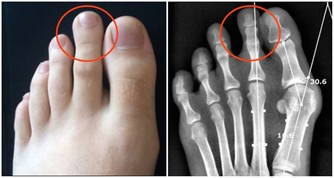

腎病

1.整個面色黎黑垢濁,下眼瞼腫,色黑,為腎久病。

2.下發暗紅色。